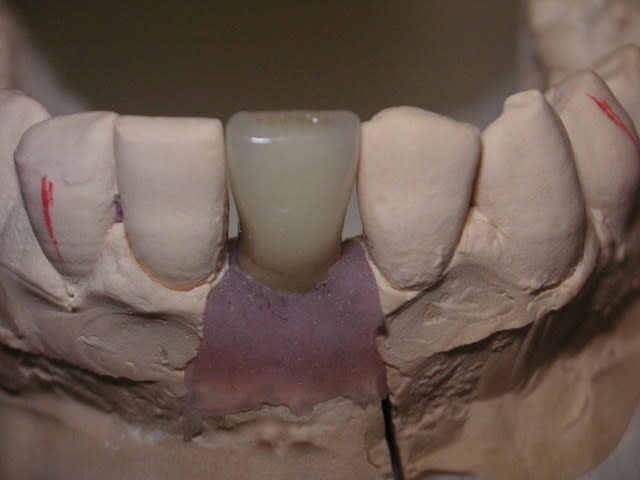

Pour remplacer 31 et 41:

Un Implant central de 3,75 ou 4,00 avec émergence de vis linguale.

Un pilier Zircone "Bifide" avec céramique montée directement dessus et fausse gencive céramique.

C'est simple, pérenne et très joli.

Un compromis pour remplacer 2 centrales 31-41

Voilà c'est mon 1er post !!